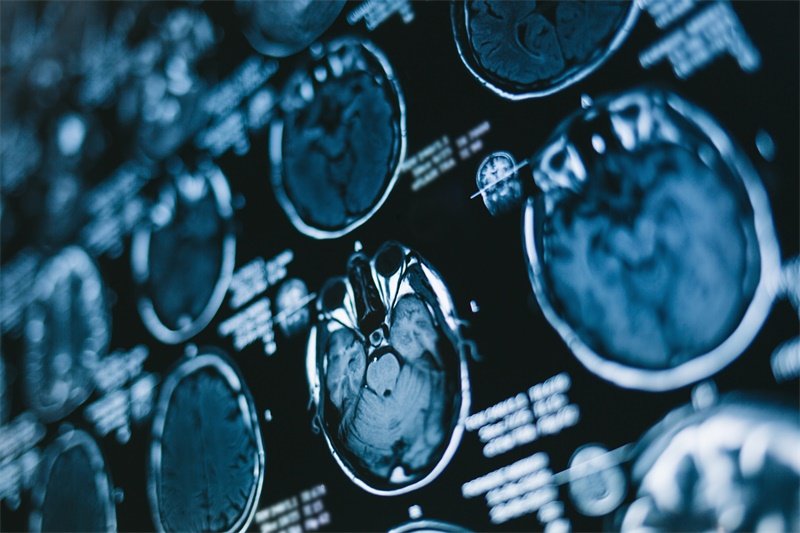

影像学检查

在临床上,影像学检查是诊断蝶鞍区占位垂体瘤的重要手段。磁共振成像(MRI)是首选的检测方法,通过对脑部的详细成像,医生能够清楚地观察到肿瘤的大小、位置及其对周围结构的影响。

诊断蝶鞍区占位垂体瘤通常需要综合考虑影像学检查和内分泌功能评估。影像学检查如MRI能帮助医生明确肿瘤的大小及位置,而血液检查则有助于检测激素水平的变化,为最终诊断提供依据。